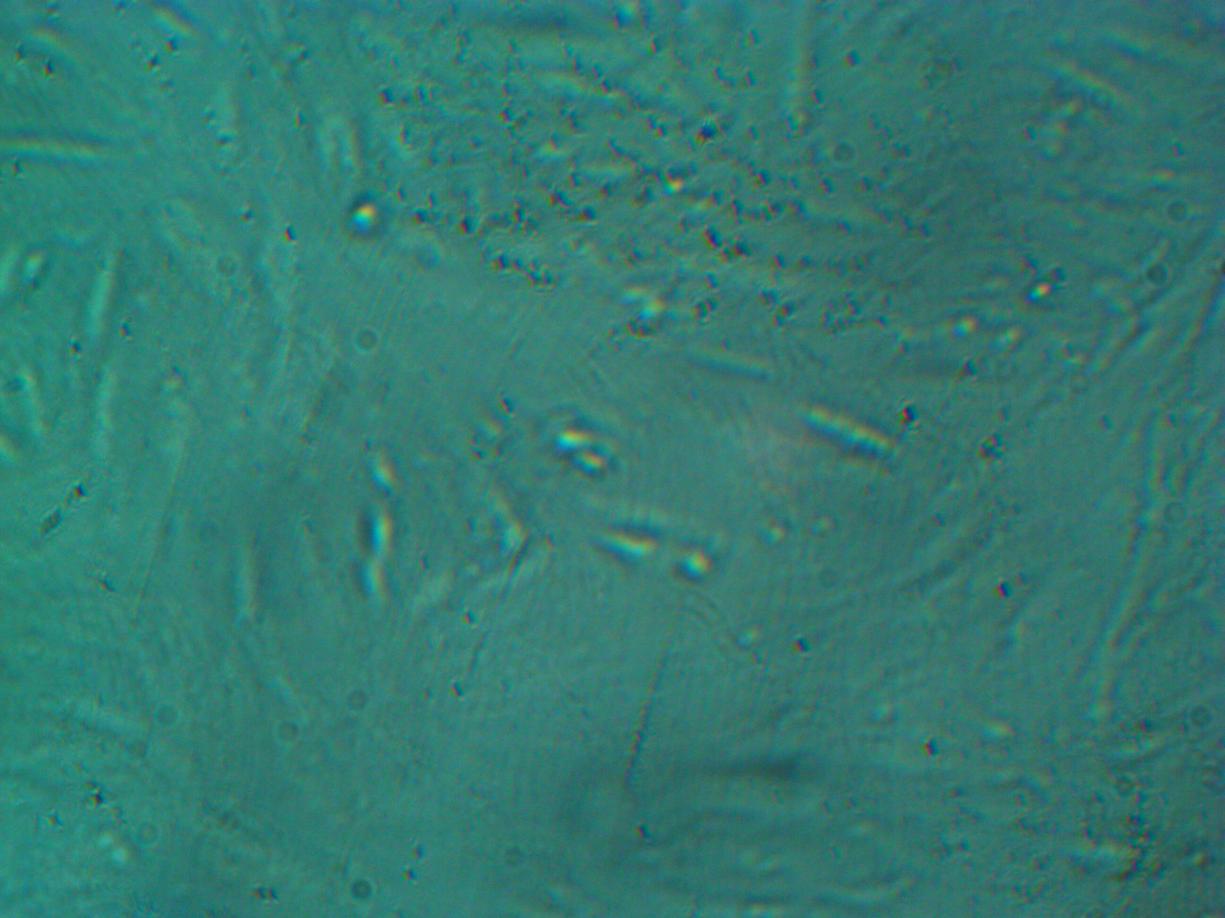

Tomorrow, we will inject 3D spheroids on the first patient and wait to see the outcome and will keep you all updated.

Respected Jahoda says in published study that, we should expect a new hair follicle/s from these injected 3D spheroidal DP cultured cells. Ofcourse i am waiting also report of versican and alkaline phosphate marker report which will conform trichogenic potential of these 3D spheroids.